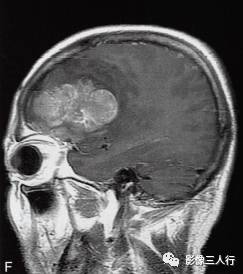

左侧额颞叶多形性胶质母细胞瘤

A.T1WI横断面;B.T2WI横断面;CFLAIR横断面;D.T1WI增强;E.T1WI增强冠状面;F.T1WI增强矢状面;G.HE×40;H.GFAR( )×40

左侧额颞叶见较大不规则囊实性肿块,大小约5.4cm×8.3cm,平扫T1WI呈低信号、T2WI呈高信号(图A、B),肿块内有斑片状囊变区;增强扫描肿块实性部分呈不均匀明显强化,囊性部分呈环形强化(图D~F)。肿块占位效应明显,周围见环形水肿(图C)。